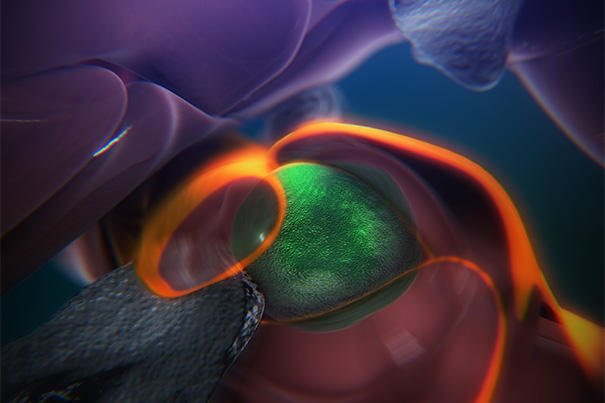

- A still from an animation that shows the steps of how blood stem cells take root in the body of a zebrafish to generate blood. (Credit: Boston Children’s Hospital/Stem Cell Research Program)

A see-through zebrafish and enhanced imaging provide the first direct glimpse of how blood stem cells take root in the body to generate blood. Reporting online in the journal Cell, researchers in Boston Children’s Hospital’s Stem Cell Research Program describe a surprisingly dynamic system that offers several clues for improving bone-marrow transplants in patients with cancer, severe immune deficiencies, and blood disorders, and for helping those transplants “take.”

The steps are detailed in an animation narrated by senior investigator Leonard Zon, director of the Stem Cell Research Program and professor of stem cell and regenerative biology at Harvard Medical School.

“The same process occurs during a bone-marrow transplant as occurs in the body naturally,” says Zon. “Our direct visualization gives us a series of steps to target, and in theory we can look for drugs that affect every step of that process.”

“Stem cell and bone marrow transplants are still very much a black box — cells are introduced into a patient and later on we can measure recovery of their blood system, but what happens in between can’t be seen,” says Owen Tamplin, the paper’s co-first author. “Now we have a system where we can actually watch that middle step. “